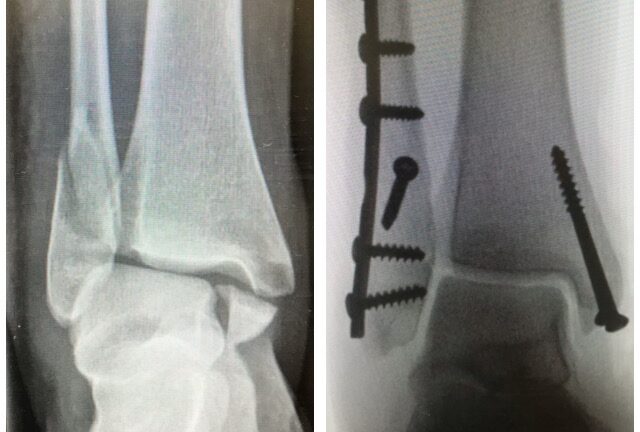

Nilkkamurtuma

Ennen – jälkeen